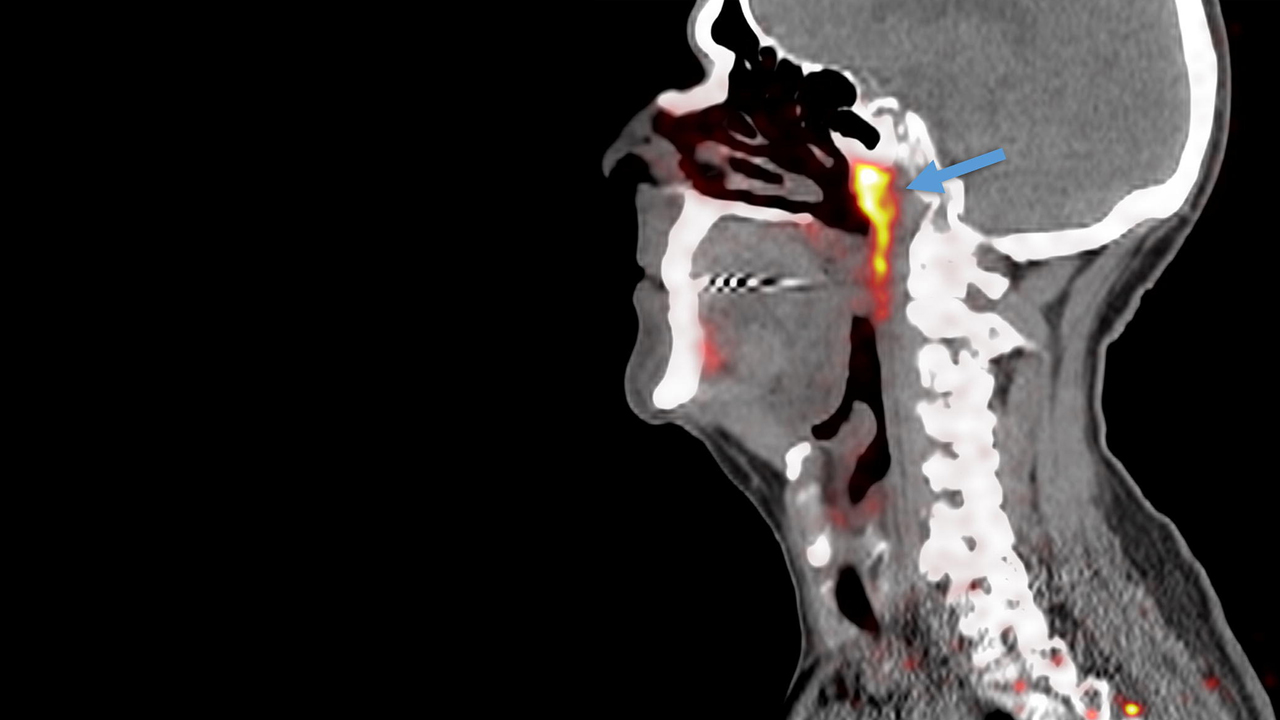

C’est l’une de ces belles histoires de ‘sérendipité’ en science, une découverte faite alors qu’on cherchait tout autre chose. En septembre 2020, des chercheurs de l’Institut du Cancer des Pays-Bas étudiaient le cancer de la prostate. Pour cela, ils utilisaient des scanners très perfectionnés (CT et PET scans) après avoir injecté aux patients un glucose radioactif. L’idée est que les tumeurs, qui consomment beaucoup de sucre, ‘s’allument’ sur les images.

La surprise sur les scanners : deux zones qui brillent de manière inattendue

Mais en regardant les images de tout le corps, les scientifiques ont remarqué quelque chose d’étrange. Dans la tête des patients, deux zones brillaient de manière très intense, alors qu’il n’y avait aucune tumeur à cet endroit. En y regardant de plus près, ils ont compris qu’ils étaient tombés sur quelque chose d’inconnu : une paire de glandes salivaires dont personne ne soupçonnait l’existence.

Il a bien fallu donner un nom à ce nouvel organe. L’équipe a décidé de les appeler les ‘glandes salivaires tubaires‘. Pourquoi ce nom ? Parce qu’elles se trouvent juste derrière le nez, dans l’espace où la cavité nasale rejoint la gorge, près d’une structure appelée le ‘torus tubaire’. Et leur fonction est la même que celle des autres glandes salivaires : produire de la salive pour lubrifier et humidifier la gorge derrière le nez et la bouche.